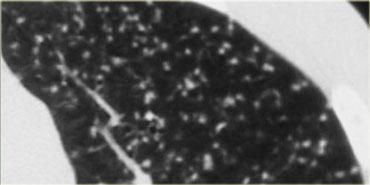

Bên trái là một trường hợp điển hình của protein phế nang với dày lan tỏa các vách liên tiểu thùy và nội tiểu thùy.

Điều này được giải thích bởi thực tế là chất liệu protein được đại thực bào vận chuyển từ khoang phế nang vào mô kẽ, do đó dẫn đến dày các vách.

Hình ảnh lát đá điên là một dấu hiệu khá không đặc hiệu.